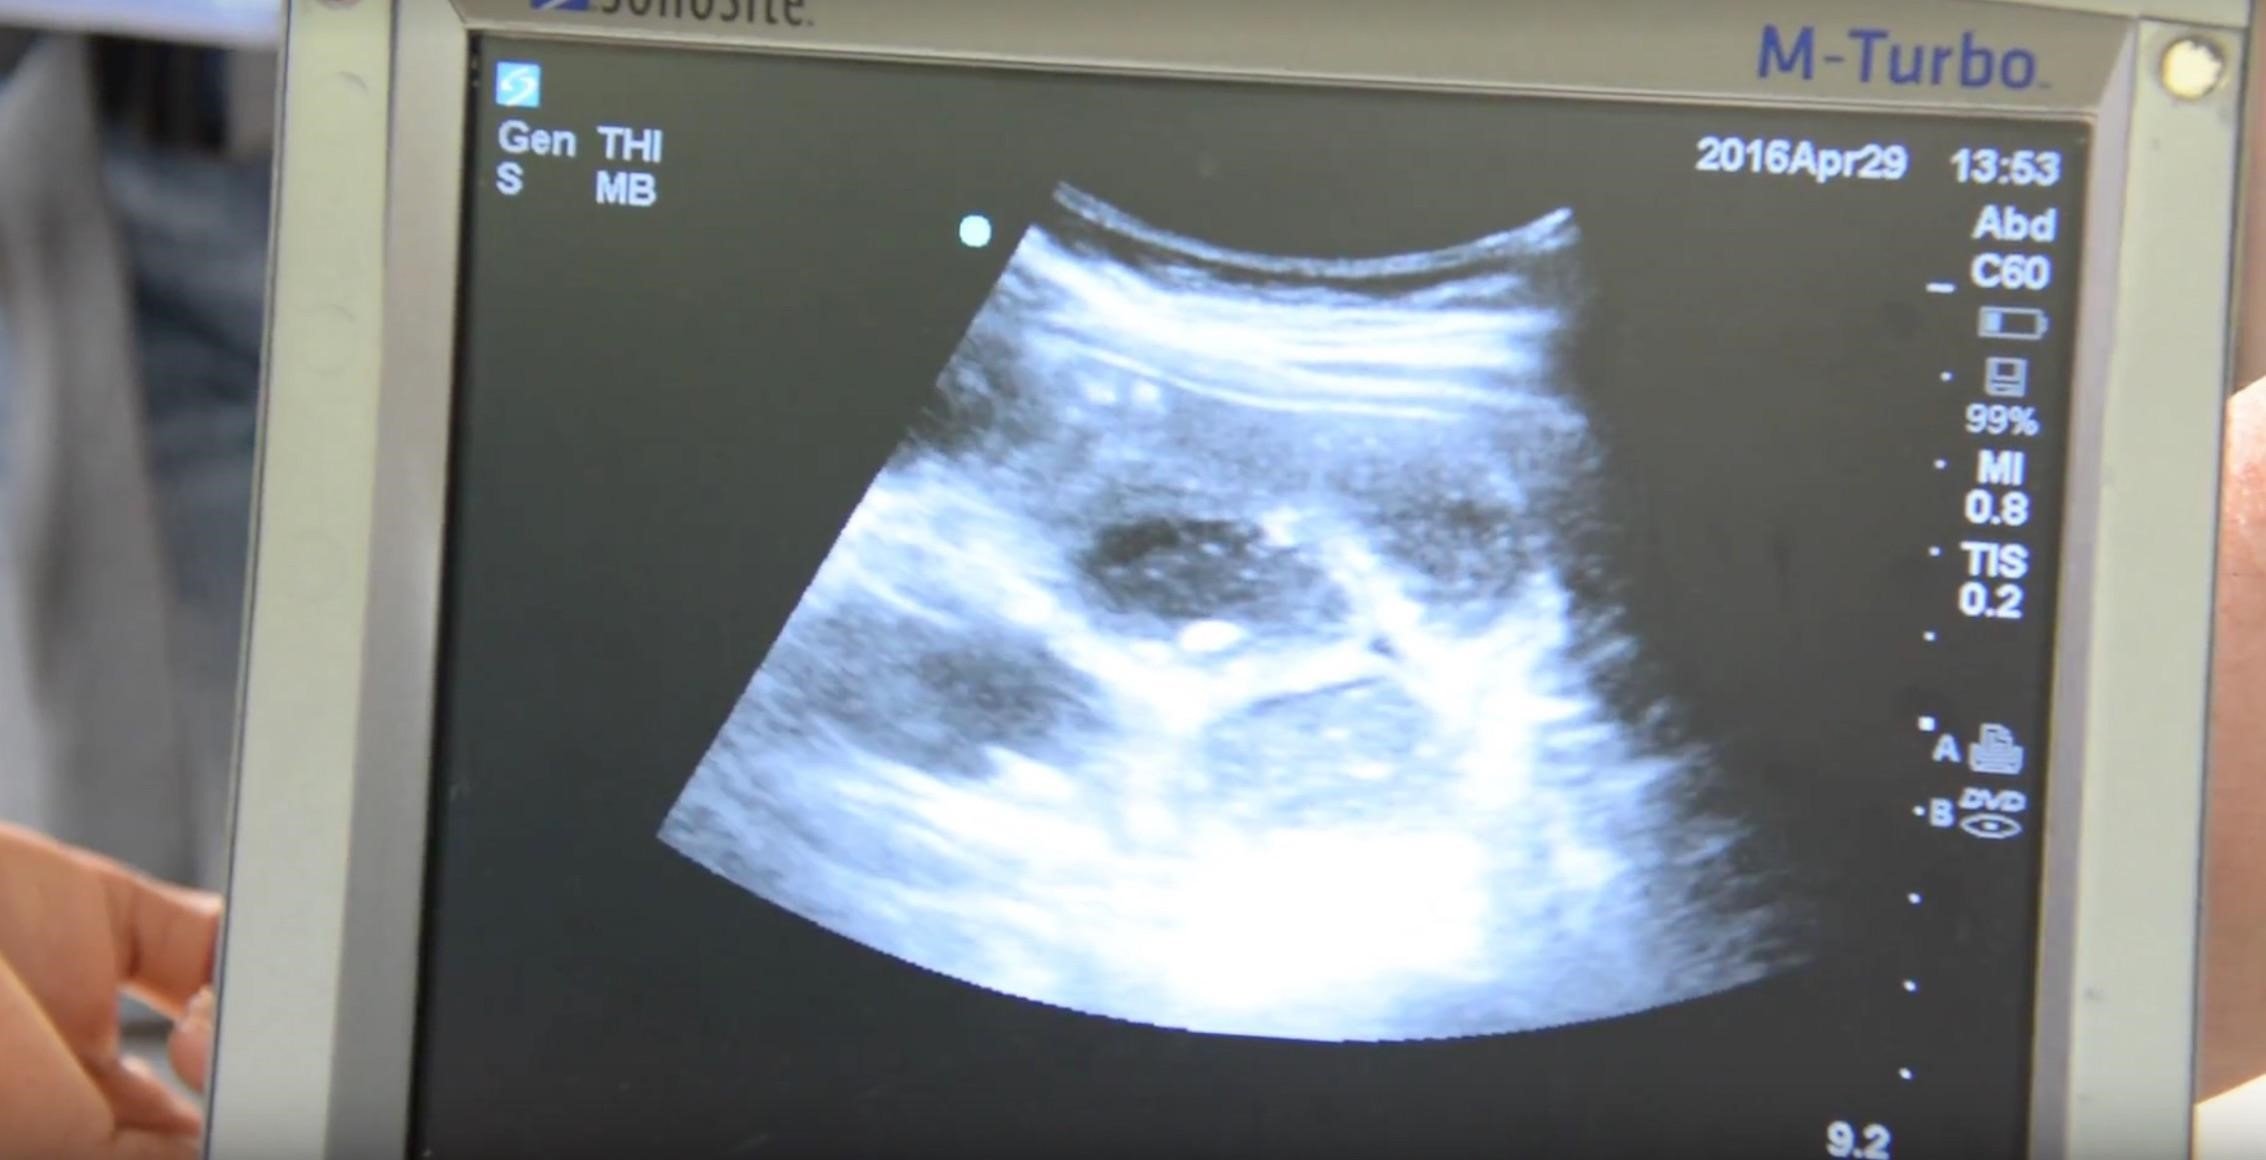

We present the case of a 15-year-old female patient with no known past medical history who presented to a transient medical clinic in the remote territory of La Moskitia, Honduras with a three-month history of poor appetite, nausea, vomiting, and worsening epigastric pain. She was initially diagnosed as gastritis at an external clinic. However, a point-of-care ultrasound examination was performed, and she was diagnosed with a small bowel obstruction (SBO) (Figure 1). During her visit, she had an episode of emesis, which demonstrated a large worm consistent with an Ascaris lumbricoides (Figure 2). The etiology of the SBO was suspected to be secondary to physical obstruction from the Ascariasis obstruction.

Figure 1. Portable ultrasound that was used to diagnose a small bowel obstruction.

Ultrasonography has been shown to be a useful adjunct in the evaluation of patients with suspected SBO as it can be performed rapidly and with high accuracy, even when performed under minimal training.6,7 The diagnosis is made based upon a small intestinal diameter of greater than 2.5 cm with abnormal peristalsis.6 A recent systematic review and meta-analysis found that ultrasound was 92.4% sensitive and 96.6% specific with a positive likelihood ratio of 27.5 and a negative likelihood ratio of 0.08.8 Therefore, ultrasound can be a valuable adjunct for making the diagnosis and is particularly valuable in areas where access to advanced imaging is limited. In this case, ultrasound was able to make the diagnosis and lead to transfer to an advanced healthcare facility, which may not have otherwise been possible.